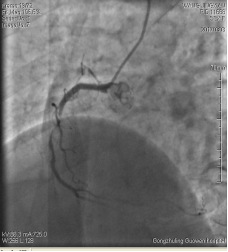

3月3日14時30分:經(jīng)右橈動脈行冠脈造影見:左主干未見明顯異常,TIMI血流3級,前降支開口正常,近中段20%狹窄,TIMI血流3級;回旋支開口正常,中遠(yuǎn)段75%狹窄,TIMI血流3級。右冠狀動脈開口正常,中段長病變,最重99%狹窄, TIMI血流3級。

圖1 回旋支遠(yuǎn)段70%狹窄 圖2 右冠脈中段99%狹窄